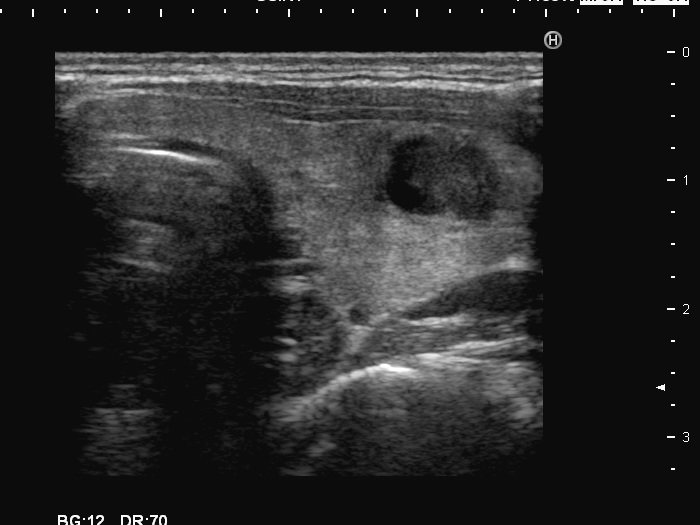

Left lobe, transverse scan

This is the usual course of Graves' disease regarding the change in echo pattern - before, during and after the activity of the autoimmune process. The only exception is the change in the size of the thyroid. In most cases, the thyroid increases during the activity of the disease, then returns to normal. However, in this patient the age counts: at the first examination, the patient was only 15-year-old.

- There are two situations in Graves 'disease where circulation is increased. At the stage of disease activity and when hypothyroidism is observed with medication. In the former case, the blood flow is almost always increased, in the latter it can be decreased and increased.